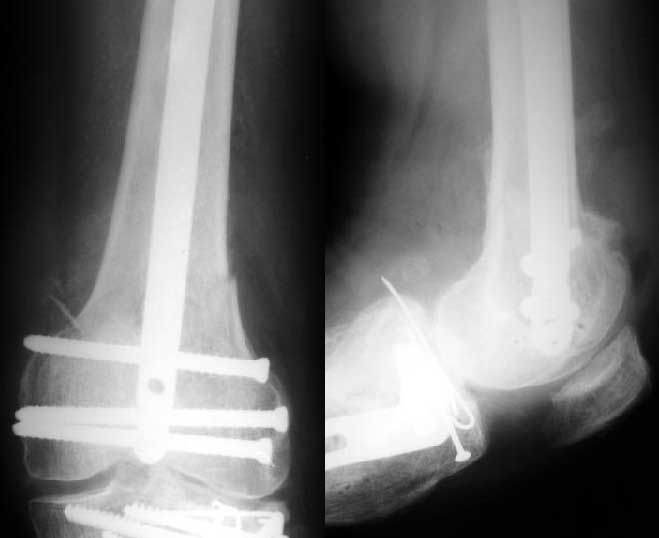

Sorry but I've just prepared postop images - attached. A solid 13 mm nail was used. A few degrees of recurvation appears to be which i missed on image intensifier. I'm still uncertain about

advantages/disadvantages of ante/retrograde nailing for such fractures.

The fixation as you have done is excellent. The locking screws on either side of the # are so apart. When we put in a supracondylar nail thro a keyhole incison in the knee, the locking bolts will be nearer the # and will be more stable allowing him to bear wt early. That was the reason the supracondylar nail was innovated. The locking is done by jig and no freehand method saving time.

the postop radiographs look excellent.

The antegrade nail in the case shown is probably into the knee joint slightly.

TAC> The antegrade nail in the case shown is probably into the knee joint slightly.

Not in this case. Though i have a couple of similar cases with 3-4 mm prominince of the nail - looks asymptomatic or covered by pre-existing problems.